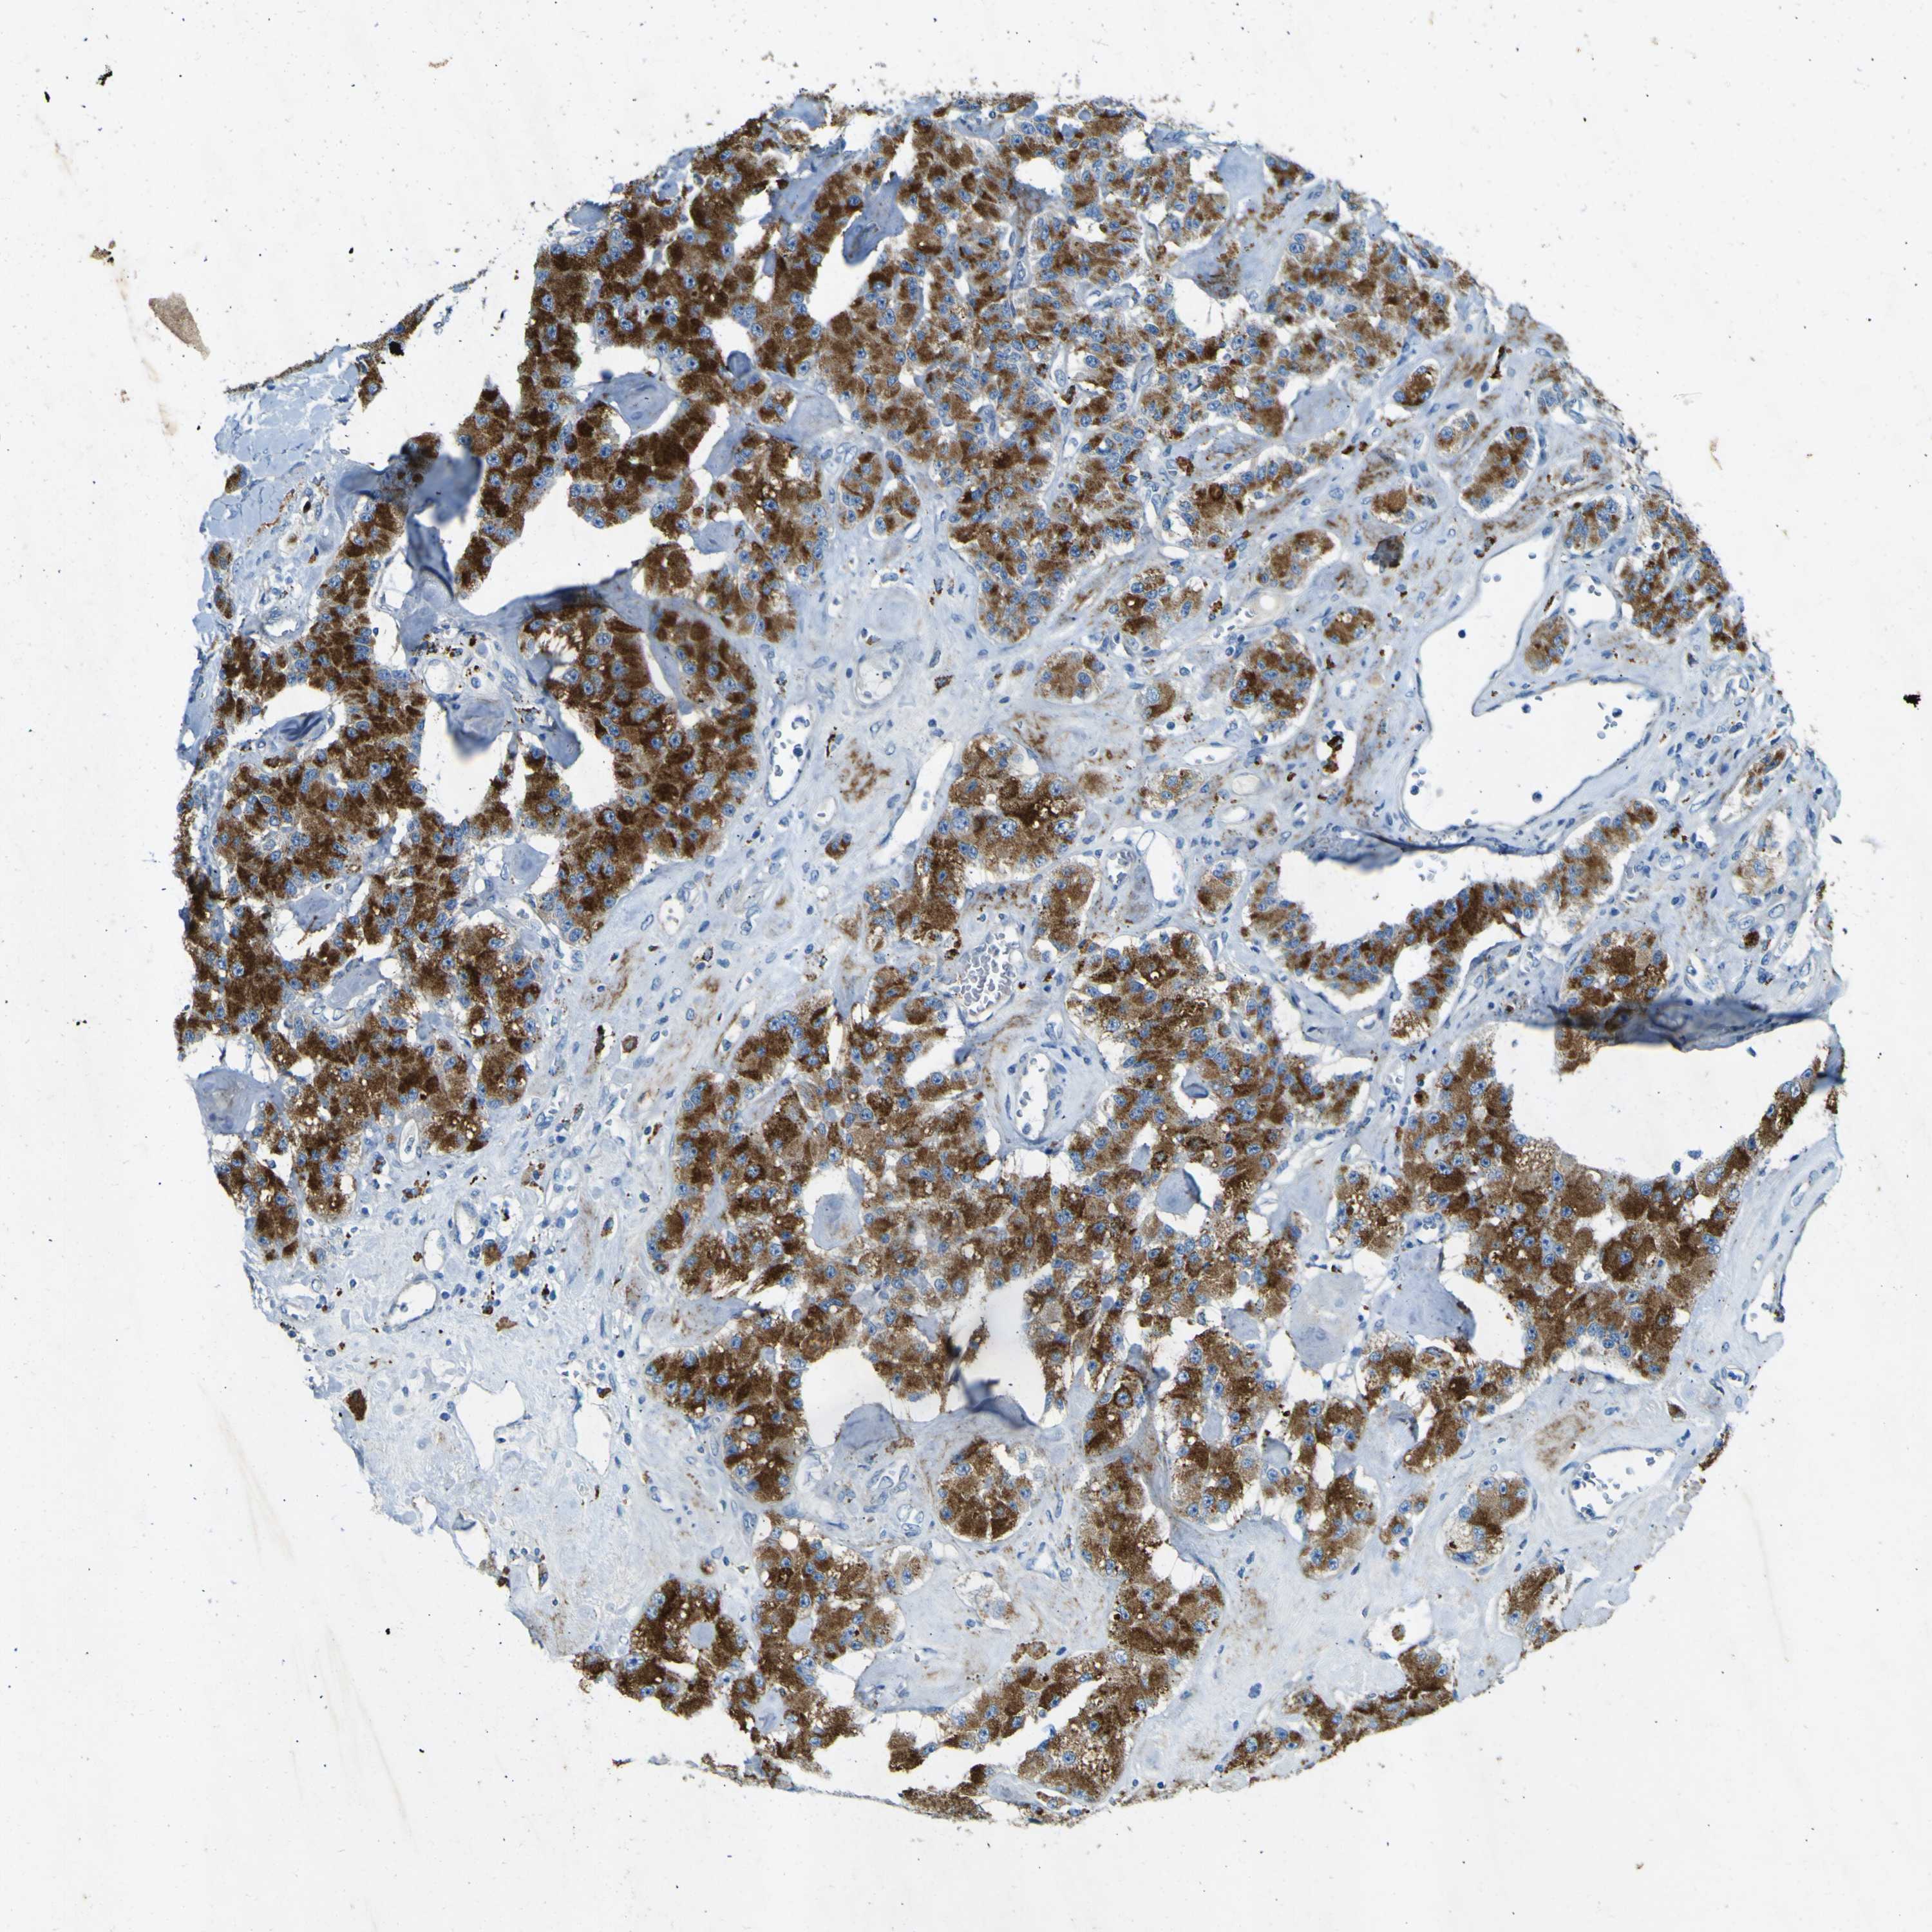

CARCINOID - Protein expressioni

A mouse-over function shows sample information and annotation data. Click on an image to view it in a full screen mode. Samples can be filtered based on level of antibody staining by selecting one or several of the following categories: high, medium, low and not detected. The assay and annotation is described here.

Antibody stainingi

Antibody staining in the annotated cell types in the current human tissue is reported as not detected, low, medium, or high, based on conventional immunohistochemistry profiling in selected tissues. This score is based on the combination of the staining intensity and fraction of stained cells.

Each image is clickable and will lead to virtual microscopy that enables deeper exploration of all samples and also displays staining intensity scores, fraction scores and subcellular localization as well as patient and tissue information for each sample.

Antibody HPA011380

Staining

High

Intensity

Strong

Quantity

>75%

Location

Nuclear

Carcinoid, malignant, NOS

Carcinoma, NOS